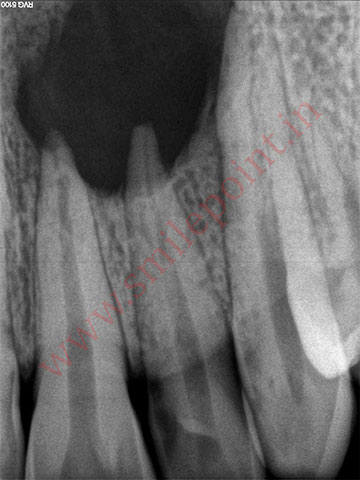

Gum Care Surgery